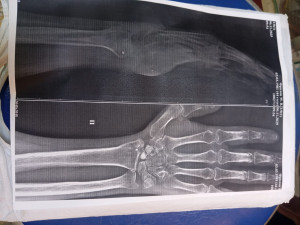

После травмы прошло 6 месяцев ,рука не работает , не скибается кисть, пальцы не работают, мучают постоянные боли, рука мёрзнет на улице , что невозможно терпеть. Чувствительность повышена , любое дотрагиваете вызывает сильнейшую боль .

Так же поврежден срединный нерв

Здравствуйте. По снимку и описанию виден несросшийся перелом ладьевидной кости с выраженными посттравматическими изменениями и признаками остеопороза, а также повреждение срединного нерва. После шести месяцев без движения и при таких осложнениях одного гипса недостаточно и требуется хирургическое лечение. Обычно выполняют фиксацию ладьевидной кости с костной пластикой, удаление инородных тел, восстановление нерва и последующую иммобилизацию. После операции назначается физиотерапия, ЛФК и реабилитация под контролем травматолога и невролога.

Здравствуйте. При таком длительном нарушении функции и данных КТ консервативное лечение уже неэффективно. Несросшийся перелом ладьевидной кости, наличие металлических и неметаллических осколков, а также признаки остеопороза и повреждение нерва требуют оперативного вмешательства. Обычно проводят ревизию раны, удаление инородных тел, остеосинтез или костную пластику, при необходимости  восстановление нерва. После этого назначают физиотерапию, реабилитацию и контрольное обследование. Без операции функция кисти скорее всего не восстановится.